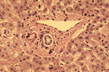

Fig 24 - Portal Space

PORTAL ARTERIOLE: Located close to the portal bile duct.Small arterioles may penetrate into the lobule.

PORTAL VEIN: Large,thin -walled perforates the limiting plate and connects with sinusoids.Terminates at the equator of the acinus were it forms the terminal portal vessel,not visible in normal conditions.

PORTAL BILE DUCT: Identifiable for its location close to the portal arteriole.

CHOLANGIOLES: Called also bile ductules and ducts of Hering are situated at the periphery of the portal space.

PORTAL LYMPHATICS: Invisible,are around vessels and bile ducts.They drain lymph from the Disse spaces to the hilus of the liver connecting with lymphtics from the glissonian capsule.

INFLAMMATORY CELLS: Presence of lymphocytes and macrophages is normal.Presence of polymorphs, eosinophils and plasma cells is abnormal.

CONNECTIVE TISSUE: Consists of interlacing type I collagen fibers.There is elastic tissue which increases with age.

PERIPORTAL LIMTING PLATE:It is a row of small hepatocytes immediately around the portal connective tissue.

SPACE OF MALL: Space between limiting plate and portal field.It contains villi .

NERVES: Sympathetic from coeliac ganglion and parasympathetic from vagus.They regulate metabolism and vascular and ductal motility.Adrenergic,cholinergic and peptidergic fibers penetrate the lobules where VIP, glucagone,substance P and calcitonin are identified.